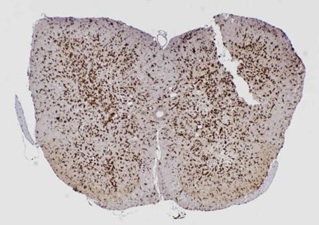

ミクログリアを染色したマウスの脊髄

蛍光顕微鏡で観察している様子